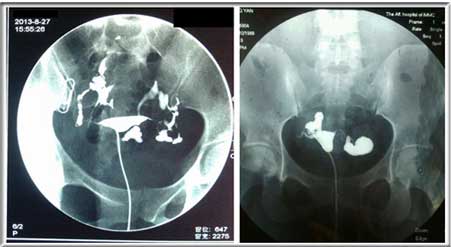

输卵管通而不畅图

1)通过输卵管造影。是目前输卵管积水的检查方法中极简便可靠的方法,x线显示,输卵管全程显影并见伞端曾粗扩张,20分钟后延迟片示两侧输卵管残留影,盆腔内无造影剂弥散。

输卵管造影检查图